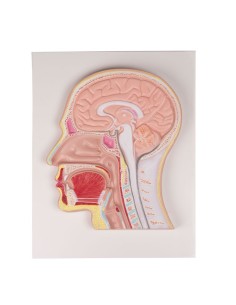

Strumenti Didattici Innovativi per l’Educazione e la Pratica Medica

Essenziali per studenti e professionisti, i nostri modelli anatomici sono strumenti didattici che permettono di osservare le strutture anatomiche con precisione, eliminando la necessità di dissezioni o studi invasivi. Sono inoltre utili per spiegare ai pazienti le patologie, rendendo la comunicazione più efficace e risparmiando tempo prezioso.